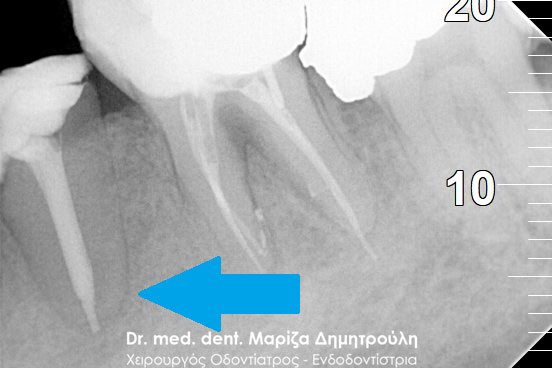

Η ασθενής επισκέφτηκε το ιατρείο μας γιατί πονούσε στον πρώτο άνω αριστερό γομφίο. Η κλινική και ακτινογραφική εξέταση φανέρωσε την αναγκαιότητα απονεύρωσης του δοντιού. Μετά το πέρας της ενδοδοντικής θεραπείας και εφόσον το οδοντικό έλλειμα ήταν μεγάλο, κρίθηκε απαραίτητη η προστασία του απονευρωμένου δοντιού με ολοκεραμική θήκη.

Αρχική κλινική εικόνα του δοντιού με το προσωρινό σφράγισμα απονεύρωσης